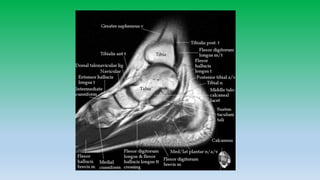

Medial aspect

Tendon: Tibialis posterior

Flexor digitorum longus

Flexor H. longus

Ligaments: Deltoid ligament

• 12. Medial ankle tendons: • Tibialis posterior attaches to navicular , cuniform and base of 1st-4rt metatarsal. Tibialis posterior tendon provides support to longitudinal arch of foot and injury can cause flat foot. • Flexor digitorum longus passes lateral to tibialis posterior tendon and inserts to distal phalanges of 2nd-5th toes. • Flexor halluces longus passes beneath sustentaculum talus and insert into base off 1st toe distal phalanx. Sheath of FHL tendon communicates with ankle joint and fluid within sheath is common.

• 14. Medial aspect Tendon: Tibialis posterior Flexor digitorum longus Flexor H. longus Ligaments: Deltoid ligament